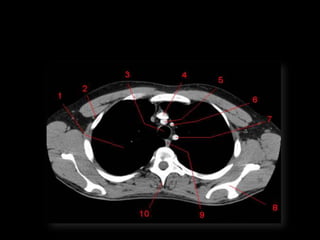

TC mediastino superior